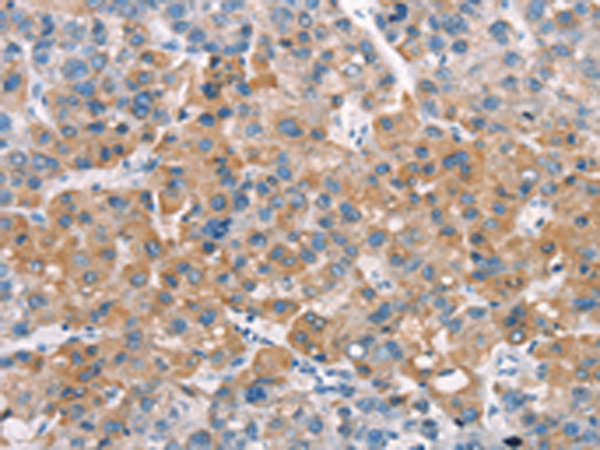

分类: 科研抗体货号: P11210别名:应用: IHC反应种属: Human, Mouse